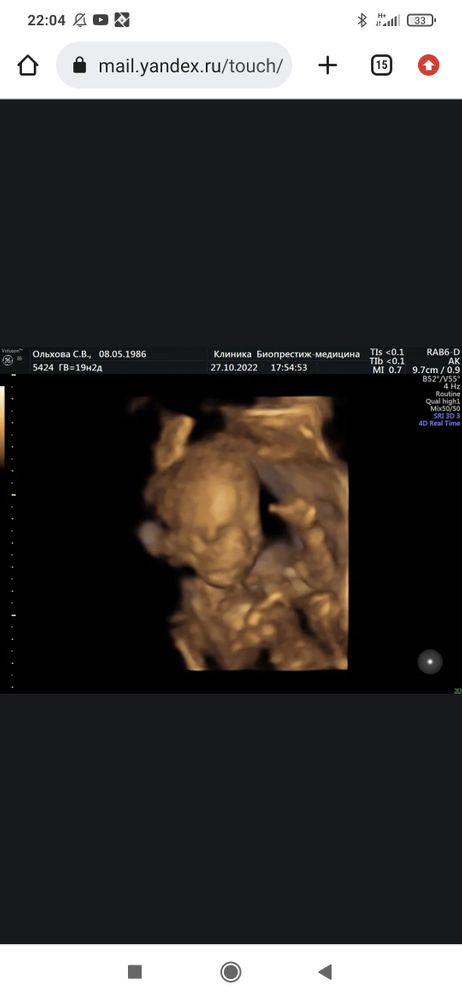

Второй скрининг. Тë С. А

Сделал. Посмотрел тщательно. Всё с ребёнком хорошо. Сердце всё норма.

Проблем тут нет.

Есть нарушение кровотока с правой стороны((

Незначительно. Но всё же... Доплер повтор через 3 нед...

Тот же путь что и с Фёдором(

Сказал давление держать, пить кардилмагнил. Но главное следить(

Изображение